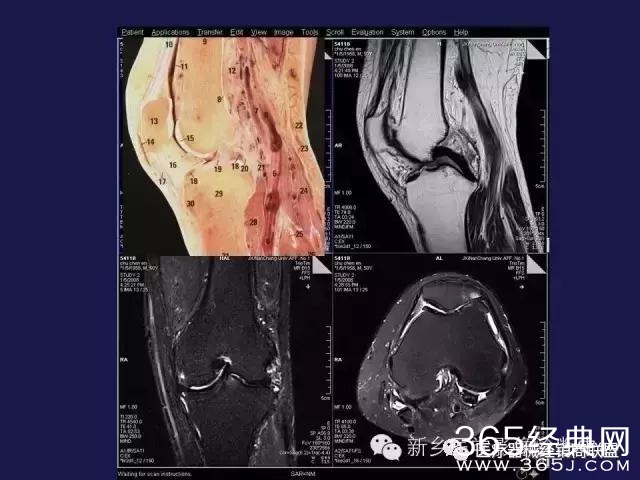

CT、MRI很难?NO,今日我们一起来学习一下如何读CT、MRI!

内行看门道:

整整90张图

强烈建议大家收藏后再观看